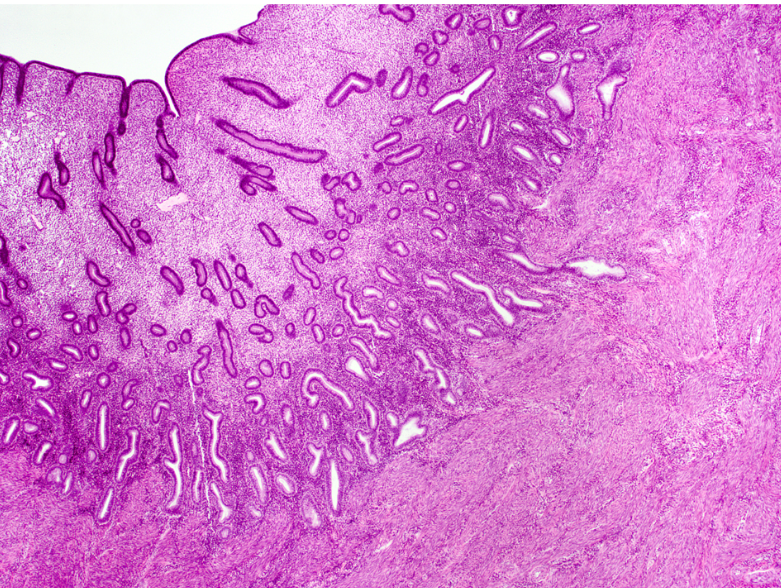

uterus

endometrium

uterine glands

myometrium